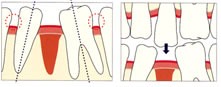

インプラント植立前

インプラント植立後

かみ合わせた状態 術後の右はレントゲン写真

インプラント植立前

インプラント植立後

かみ合わせた状態 術後の右はレントゲン写真